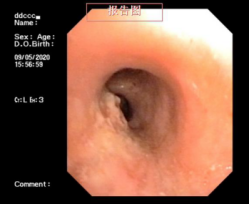

贺女士近段时间因呼吸困难到我院呼吸内科就诊,经支气管镜检查后,发现是声门下处因瘢痕体质出现了瘢痕挛缩狭窄,几乎完全堵塞气道。

“人的正常气管直径在10-15mm左右,而该患者气管最狭窄处直径仅2mm,每呼吸一次都伴随着痛苦,并且随时可能因痰堵引起窒息!”呼吸内科副主任刘碧翠说。他迅速带领介入团队确定治疗方案,并成功使用球囊扩张技术为患者开展手术。该技术将球囊通过支气管镜的嵌道送入狭窄的气道,然后通过向球囊内施加压力,对气道进行物理扩张。仅1个小时,患者显著狭窄的气道被打通扩开,患者又可以畅快呼吸了。